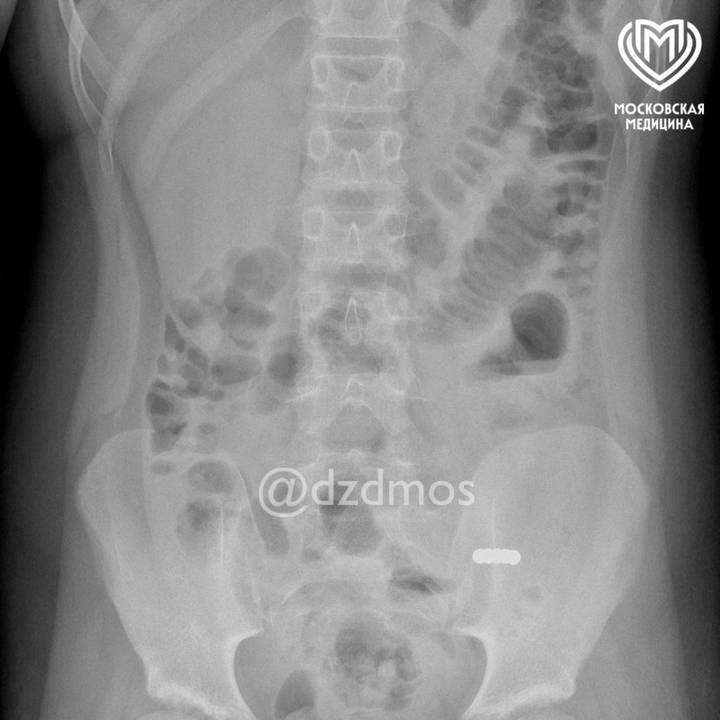

По словам представителей ведомства, девочка пожаловалась родителям на рвоту и жидкий стул. Доктора сделали ей рентген и обнаружили мелкие инородные предметы. Оказалось, что шарики попали в разные петли и сдавили их между собой собственным притяжением друг к другу, из-за чего в кишке образовались «дырки».